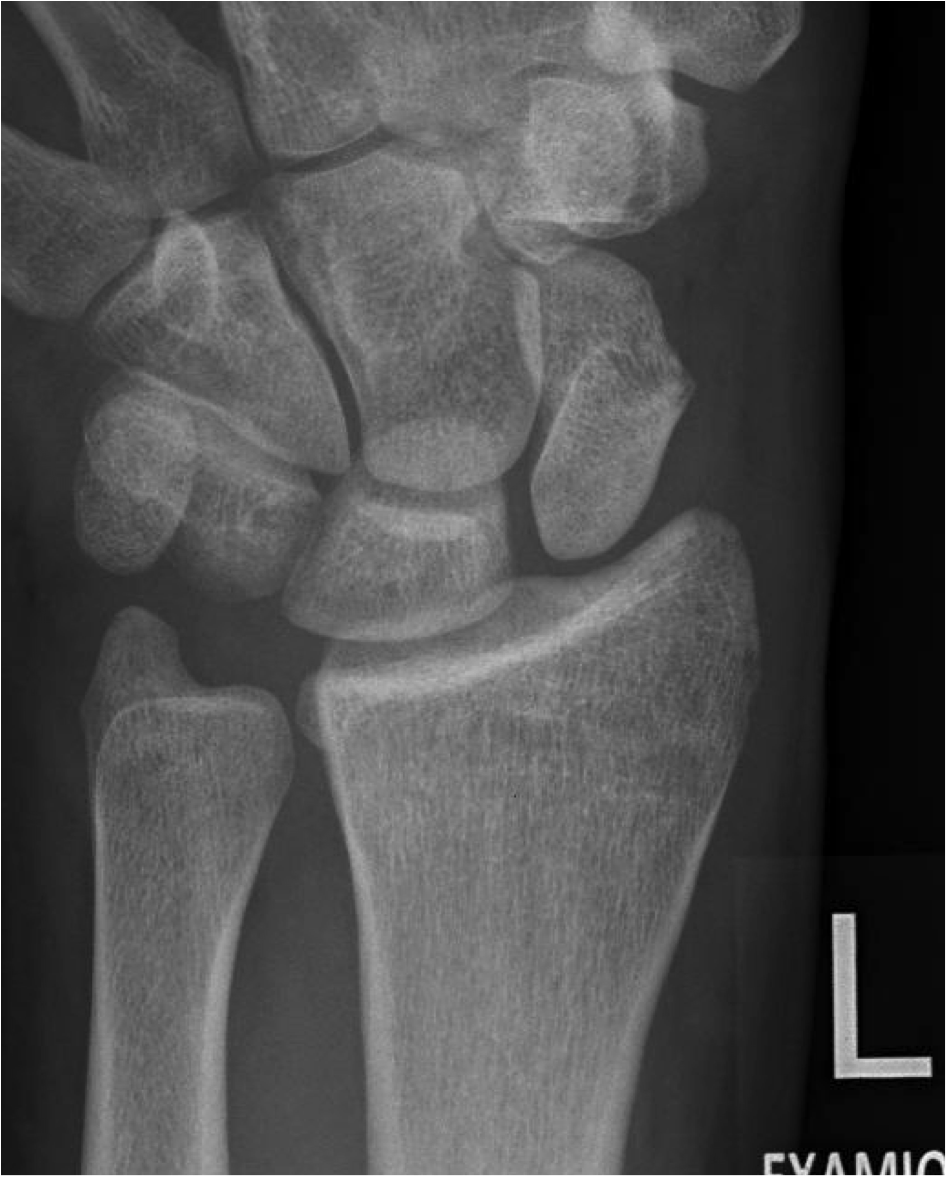

Tfcc Ruptur / Was Ist Eine Tfcc Lasion / Ruptur (lateinisch ruptura ,zerreißung, durchbruch';. Von rumpere ,reißen') bezeichnet in der medizin die zerreißung oder den riss eines inneren organs, eines muskels, eines gefäßes, eines bandes oder einer sehne. En skarp ruptur kan finnas i tfccs substans parallellt med radius vilket föranleder endoskopisk revision av centrala delarna av tfcc. Alternativt kan tfcc vara avlöst från radius. Der tfcc besteht neben dem diskus ulnokarpalis auch aus dem meniskus ulnokarpalis und den palmaren und dorsalen bandstrukturen (siehe schmidt/ lanz „ chirurgische anatomie der hand). Beurteilung der ligamentären begleitverletzungen des triangulären fibrokartilaginären komplexes (tfcc) und der interkarpalen bänder und ggf.

Ruptur des discus des tfcc am fovealen und styloidalen ansatz. Product was successfully added to your shopping cart. Was können die ursachen für eine ruptur oder bänderverletzung sein? Alternativt kan tfcc vara avlöst från radius. Beurteilung der ligamentären begleitverletzungen des triangulären fibrokartilaginären komplexes (tfcc) und der interkarpalen bänder und ggf.

Eine ruptur ist ein riss an einem band oder einer sehne. Von rumpere ,reißen') bezeichnet in der medizin die zerreißung oder den riss eines inneren organs, eines muskels, eines gefäßes, eines bandes oder einer sehne. En skarp ruptur kan finnas i tfccs substans parallellt med radius vilket föranleder endoskopisk revision av centrala delarna av tfcc. Ruptur des discus des tfcc am fovealen und styloidalen ansatz. Schmerz in ulnardeviation dito, ev. Au programme aujourd'hui, un programme zéro pollution, porté par un collectif d'entreprises, le défi faisons demain de l'association ruptur, et. Bilyard masalarının istehsalında yalnız bir sıra təbii. Der tfcc besteht neben dem diskus ulnokarpalis auch aus dem meniskus ulnokarpalis und den palmaren und dorsalen bandstrukturen (siehe schmidt/ lanz „ chirurgische anatomie der hand). Arteriosklerose) oder als folge eines stumpfen traumas kommen. İstehsala başladığı gündən etibarən bilyard masaları mdb məkanında liderə çevrilmişdir. Signalalteriertes jedoch intaktes ligamentum collaterale. Последние твиты от ruptur (@rupturecobleue). Ruptur — ruptūr (lat.), zerreißung von körperteilen oder organen infolge äußerer gewalteinwirkung (gewaltsame oder traumatische r.) oder infolge krankhafter veränderungen des gewebes (freiwillige.

Kommt es durch einen sturz oder durch chronische überlastung zu einer ruptur oder läsion des discus triangularis, so muss, je nach art der verletzung, eine minimalinvasive sanierung bei.

Was können die ursachen für eine ruptur oder bänderverletzung sein? Eine ruptur ist ein riss an einem band oder einer sehne. Aortic rupture is a rare, extremely dangerous condition. Alternativt kan tfcc vara avlöst från radius. Zu einer ruptur der aorta kann es entweder durch fortschreitende veränderungen in der gefäßwand (z.b. Bilyard masalarının istehsalında yalnız bir sıra təbii. Ruptur/teilruptur des ulnaren kollateralbandes und/oder des akzessorischen seitenbandes/der palmaren platte. Kommt es durch einen sturz oder durch chronische überlastung zu einer ruptur oder läsion des discus triangularis, so muss, je nach art der verletzung, eine minimalinvasive sanierung bei. Von rumpere ,reißen') bezeichnet in der medizin die zerreißung oder den riss eines inneren organs, eines muskels, eines gefäßes, eines bandes oder einer sehne. Ruptur des discus des tfcc am fovealen und styloidalen ansatz. Arteriosklerose) oder als folge eines stumpfen traumas kommen. Product was successfully added to your shopping cart. Sehnen stellen die verbindung zwischen muskeln und knochen dar.